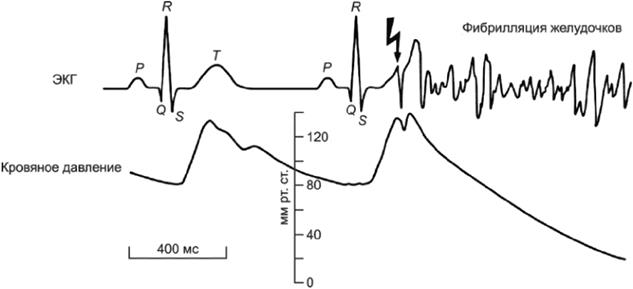

Примечание - Фибрилляция желудочков - это ненормальный сердечный ритм, при котором происходит непоследовательное, хаотическое возбуждение и сокращение отдельных желудочковых волокон.

3.2.7 период уязвимости (vulnerable period): Сравнительно небольшая часть сердечного цикла, в течение которой сердечные мышечные волокна находятся в состоянии неоднородной возбудимости, и при воздействии на них электрического тока достаточной силы происходит фибрилляция желудочков.

Примечание - Период уязвимости соответствует первой части зубца T на электрокардиограмме, что составляет приблизительно 10% длительности сердечного цикла.

Порог ФЖ зависит от физиологических характеристик (строение тела, состояние сердца и т.п.), а также от электрических параметров (длительность и путь протекания тока, характеристики тока и т.п.). Описание сердечной деятельности показано на рисунках А.16 и А.17 и в приложении И.

Для синусоидального переменного тока частотой 50/60 Гц происходит заметное снижение порога ФЖ при времени протекании тока более длительности одного сердечного цикла. Причина этого явления состоит в том, что неоднородность возбужденного состояния сердца увеличивается вследствие вызванных током экстрасистол.

Если время воздействия менее 0,1 с, то ФЖ может возникать при токах более 500 мА, а при токах порядка несколько ампер ее возникновение вероятно, только если ток снизится в течение периода уязвимости. При ударах током подобной силы и длительностью более одного периода сердечного цикла может произойти обратимая остановка сердца.

Примечание - Цифры на рисунке соответствуют последовательным стадиям распространения возбуждения.

P - интервал деполяризации предсердий; QRS - интервал деполяризации желудочков; T - интервал реполяризации желудочков

Рисунок А.16 - Период уязвимости желудочков в течение сердечного цикла

P - интервал деполяризации предсердий; ORS - интервал деполяризации желудочков; T - интервал реполяризации желудочков

Рисунок А.17 - Инициирование ФЖ в течение периода уязвимости. Изменения электрокардиограммы (ЭКГ) и кровяного давления